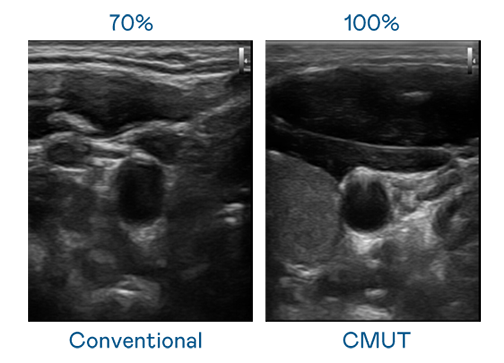

CMUT 技术是一种用电容式微机电元件来产生超音波讯号的技术。与传统 PZT 压电式技术相比,CMUT 频宽增加 30%,更宽频的超音波讯号让影像解析度大幅提升,是实现高影像品质医疗超音波扫描、促进精准医疗发展的关键技术。

超音波影像的解析度高低,首先取决于探头能发出的讯号频宽。ng28南宫相信品牌力量 CMUT 可提供高清晰的超音波讯号,提供高频宽、高灵敏度、影像纹理细节更高的超音波影像,协助医护人员缩短影像判读时间及利用精准的医疗影像进行诊断。